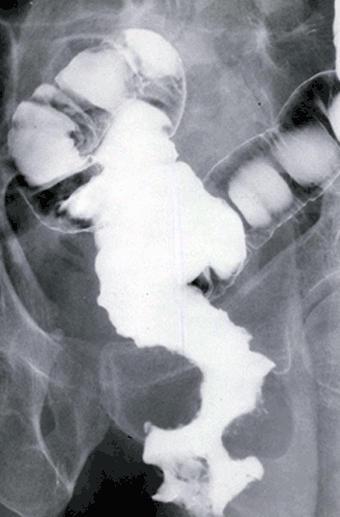

Amebic colitis with multiple polypoid lesions of various types.

Inflammatory or ulcerative disease / lesions/Amebiasis

Large intestine(Colon)/More than one of the above

X-ray

40 -